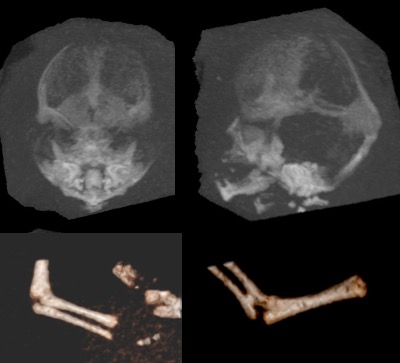

c’est un examen invasif car soumettant le foetus à des rayons X ; il est néanmoins nécessaire pour étudier l’os, dans le but de :

- préciser la ou les sutures atteintes

- rechercher une faciosténose (Crouzon, Apert, Pfeiffer, Saethre-Chötzen) qui peut avoir un impact pronostique majeur

- rechercher d’autres anomalies du squelette :

- syndactylie (syndrome d’Apert)

- malformations des pouces (syndrome de Pfeiffer)

- synostose radio-cubitale (Antley-Bixler)

- brièveté des os longs (nanisme tanathophore)